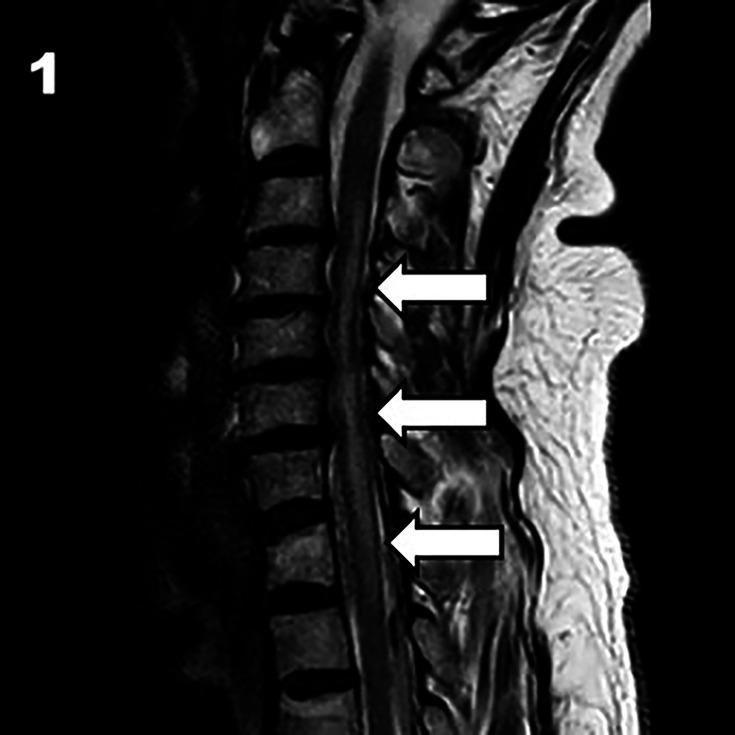

Spinal cord infarction (SCI) is associated with poor clinical outcome. Intravenous thrombolysis (IVT) is a well-established treatment for cerebral ischaemic stroke. However, its efficacy in SCI is unknown.

We present a case of acute spinal cord ischaemia with significant improvement following thrombolysis and review the current literature to explore the safety and feasibility of this treatment.